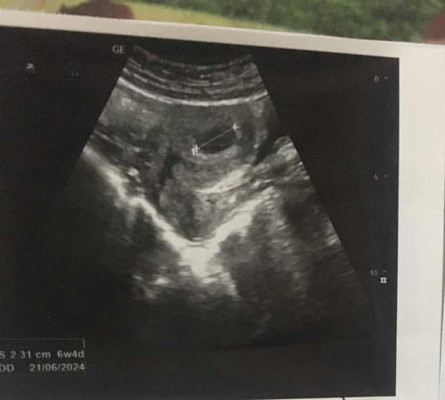

เจอน้องกี่วิคค่ะ

6วิค4วันยังไม่เจอตัวน้องเรยค่ะแม่ๆเจอน้องตอนกี่วิคค่ะ😥